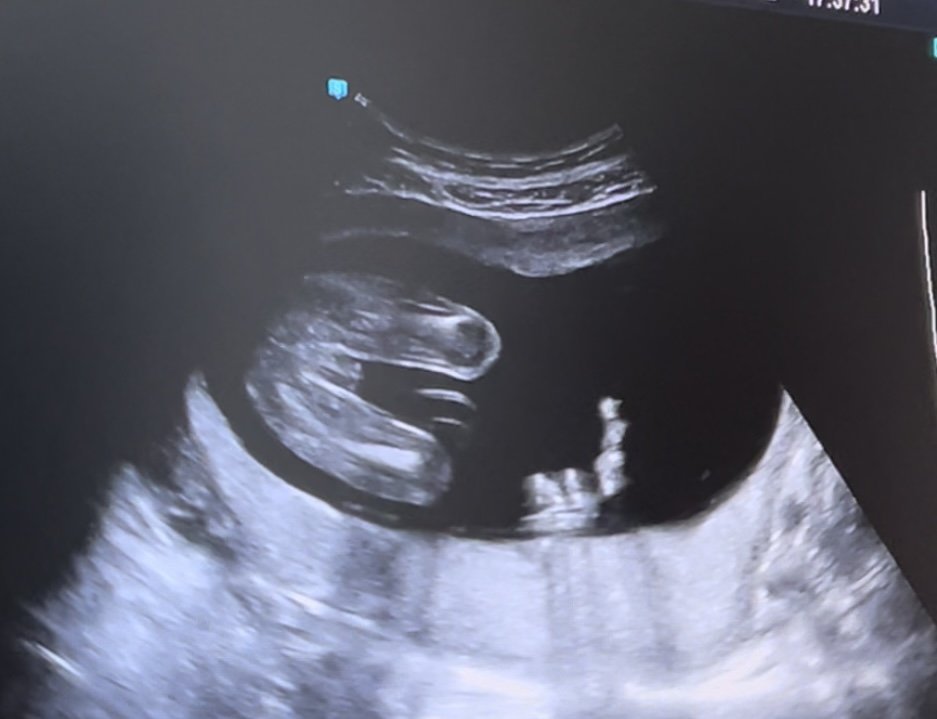

Здравейте ,доктора ми каза че очакваме момиченце ,но все пак прикачвам снимка и ще се радвам да ми кажете на вас на момиченце ли ви прилича😁Благодаря предварително.

Момиченце е, да. Честито 🤗

Имаме подобна снимка на дъщеря ми.☺

По момичешко от това, няма накъде. Честито, живо и здраво бебче, нека изпълни с радост дома ви.

Прилича ми на бебе, момиче, момче живо и здраво да е, по важно от това няма.